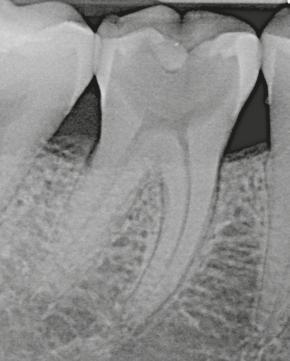

Trattamento canalare ortogrado dell’elemento 46: sagomatura con Absoulte shaper, detersione con Ipoclorito di Sodio e EDTA attivati con Ultrasuoni, otturazione con tecnica della compattazione verticale a caldo della guttaperca.

Caso clinico Dr. Filippo Cardinali Lastra pre-operatoria Lastra post-operatoria